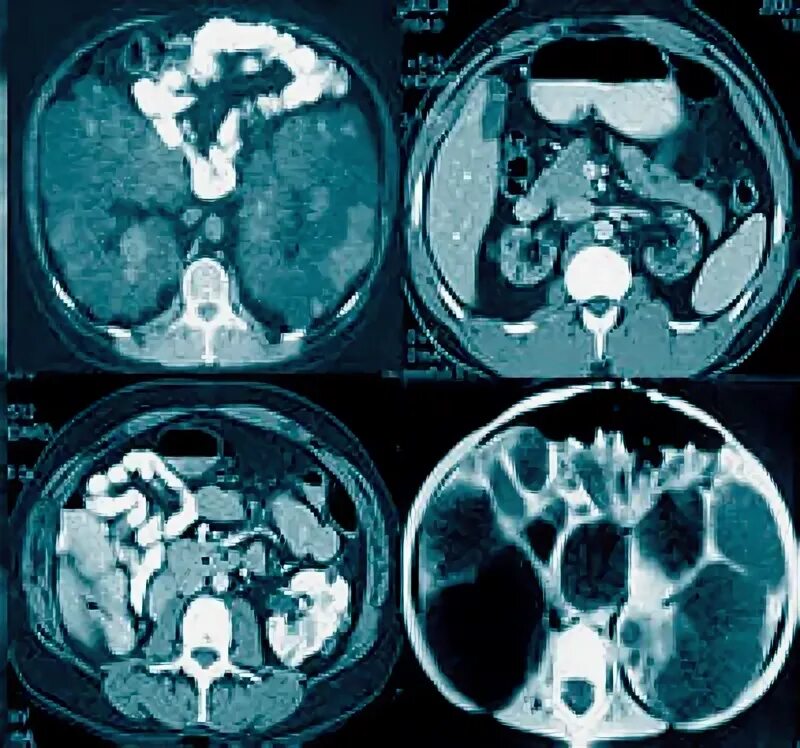

Кт почек с контрастированием как проводится